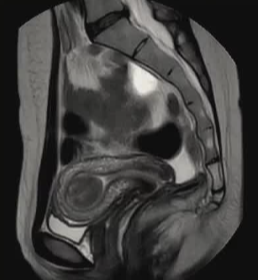

| 孤立性粘膜下子宫肌瘤 | 多发子宫肌瘤 |